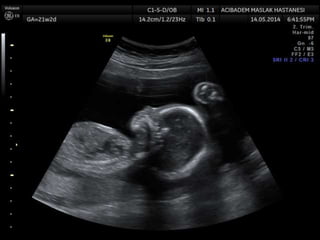

Amniotic band sequence:

Amniotic band sequence refers to a highly variable

spectrum of congenital anomalies that occur in

association with amniotic bands